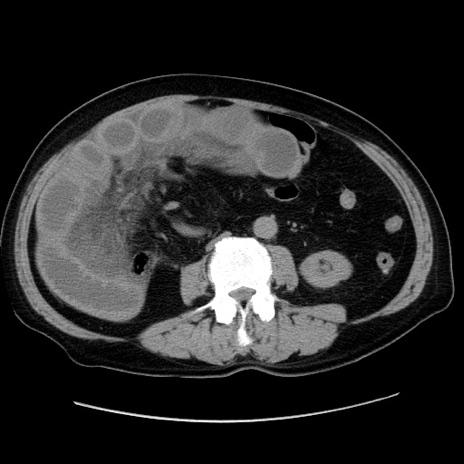

冠状断像

【症例】80歳代男性

【現病歴】約6時間前から臍下部痛が出現。次第に腹部膨隆・背部痛も生じてきたため来院。背部痛の場所は変化しない。

【身体所見】意識清明、BT 36.3℃、BP  131/87mmHg、P 87bpm、SpO2 100%(RA)、臍周囲自発痛・圧痛あり、反跳痛なし、自発痛部位に一致して板状硬あり、腹部膨隆、腸雑音減弱、CVA tenderness両側陰性。

【データ】WBC 19600、CRP 0.33